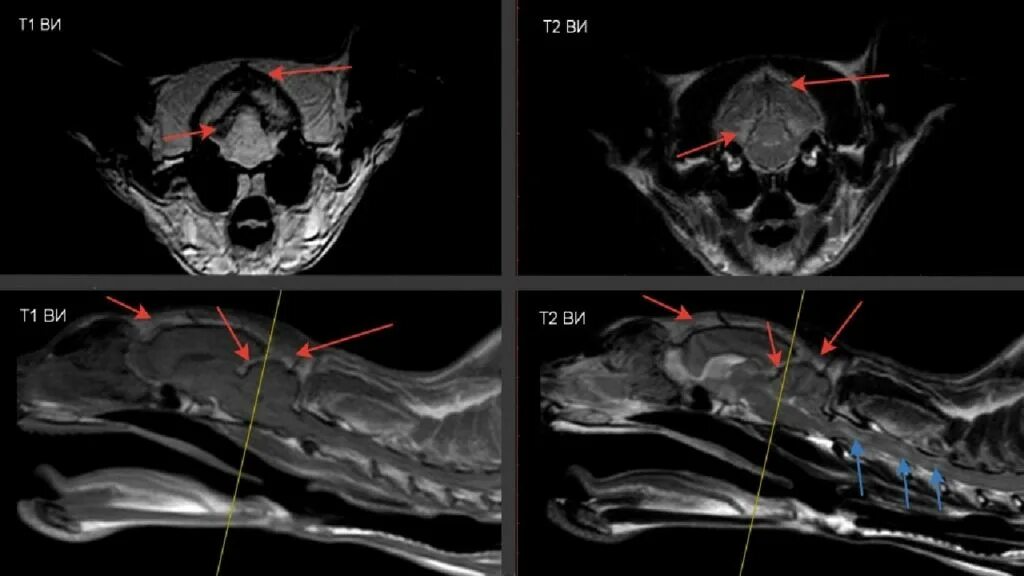

Bypass mrt